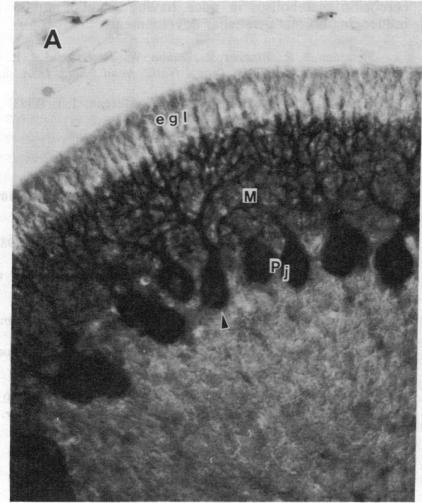

The cerebellum-specific hexadecapeptide cerebellin has been localized by immunocytochemical means to the perikarya and dendrites of cerebellar Purkinje cells. Biochemical analysis using ion-pairing HPLC shows cerebellin to first appear 5 days after birth, whereafter levels rise to a maximum at 25 days postpartum, and then decline to stable adult values. This same pattern of development occurs with a lag of approximately 5 days for the major metabolite of cerebellin, des-Ser1-cerebellin. The immunocytochemical picture of cerebellin in developing Purkinje cells mirrors the biochemical data. These results show that cerebellins represent unique quantifiable markers for the investigation of Purkinje cell maturation and lend support to the feasibility of using unique endogenous peptides to chart neurodevelopment.

小脑特异性十六肽小脑素已通过免疫细胞化学方法定位到小脑浦肯野细胞的胞体和树突。使用离子对高效液相色谱法进行的生化分析表明,小脑素在出生后5天首次出现,此后水平在产后25天升至最高,然后降至稳定的成年值。小脑素的主要代谢产物去丝氨酸1-小脑素的发育模式相同,但滞后约5天。发育中的浦肯野细胞中小脑素的免疫细胞化学图像与生化数据相符。这些结果表明,小脑素是研究浦肯野细胞成熟的独特可量化标志物,并支持使用独特的内源性肽来描绘神经发育的可行性。